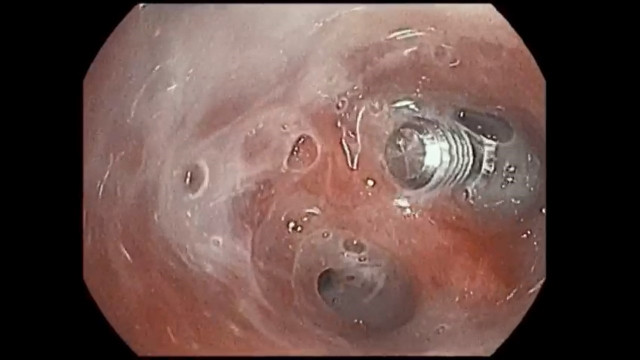

Tornillo intrabronquial extraido a una paciente de 70 años de edad en el hospital Vithas Vigo.

Una mujer de 70 años de edad ha sido intervenida en el Hospital Vithas de Vigo para la extracción de un tornillo de titanio de uso dental de sus bronquios, que la paciente había aspirado sin darse cuenta varios meses antes.

La mujer no fue consciente de que había aspirado un cuerpo extraño, que resultó ser un tornillo de titanio de los que se emplean habitualmente en los implantes dentales, de 9 mm de longitud por 5,5 mm de diámetro. El tornillo fue aspirado en algún momento entre la segunda y la tercera intervención, por lo que estuvo alojado en un bronquio unos 8 meses.

Finalmente, se llevó a cabo una broncoscopia, en la que también participaron anestesista y enfermera, dada la edad y complicaciones de la mujer. Con ayuda del videobroncoscopio, el médico pudo localizar el tornillo que, afortunadamente, estaba liberado de tejido, y pudo extraerlo con unas pinzas.

Dado que no existen casos de cuerpos extraños intrabronquiales de titanio en la literatura médica, el neumólogo de Vithas Vigo ha concluido que "posiblemente el titanio no provoque reacción de cuerpo extraño en la vía aérea y no forme tejido de granulación".